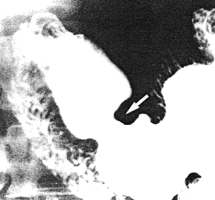

![]() |

| Fig. 27.2. Reflux of barium (arrow) from the duodenum into the pyloric sphincteric cylinder, which is relaxed |

As indicated previously (Chap. 3), the muscular part of the pyloric ring is considered to be the terminal annular thickening of the pyloric sphincteric cylinder, as described by Cunningham (1906), Forssell (l913) and Torgersen (l942). The cylinder, which is 3.0 to 4.0 cm in length, normally contracts in a segmental (as opposed to "peristaltic") way (Chap. 13). As the ring forms an inherent part of the cylinder, it closes and opens with contraction and relaxation of the cylinder respectively. In all subjects these contractions were normal. Reflux in the 5 subjects occurred either during maximal relaxation of the sphincteric cylinder, (Fig. 27.2), or when it was in a state of partial contraction (Fig. 27.3). It never occurred during maximal contraction of the cylinder.